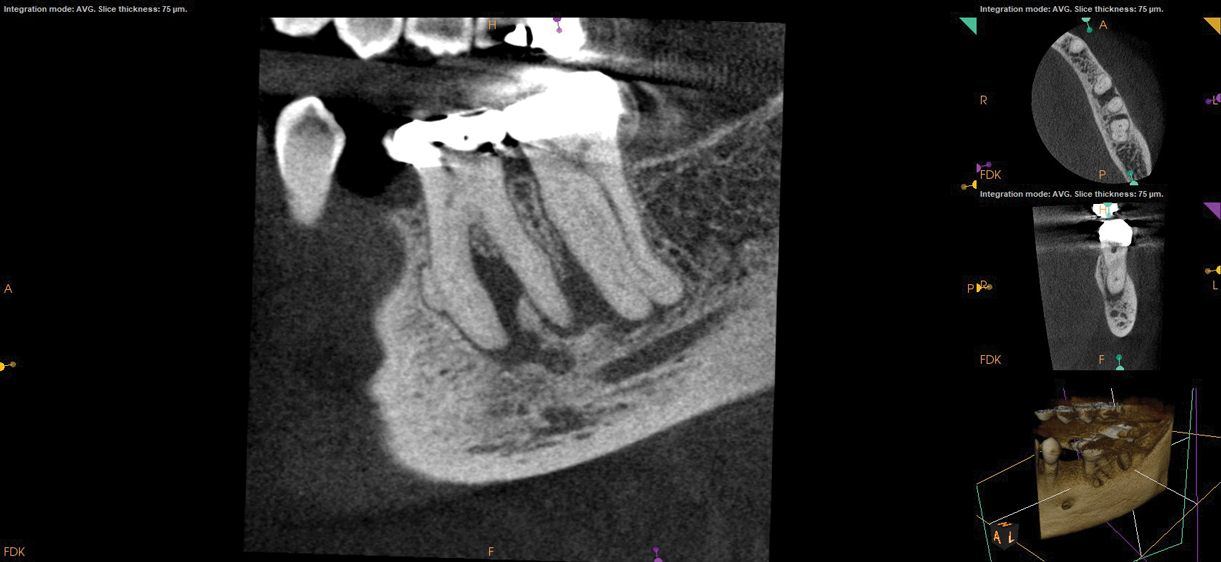

Fig 1. NSRCT can have high success, even with risk factors like periapical pathology associated, as depicted in this case presentation. Fig 1: Preoperative periapical radiograph showing AP. Fig 2: Preoperative CBCT. Fig 3: Immediate postoperative periapical radiograph. Fig 4: Three-month follow-up CBCT showing reduction of periapical radiolucency. Fig 5: One-year follow-up periapical radiograph showing resolution of periapical radiolucency.

Fig 1 through Fig 5. NSRCT can have high success, even with risk factors like periapical pathology associated, as depicted in this case presentation. Fig 1: Preoperative periapical radiograph showing AP. Fig 2: Preoperative CBCT. Fig 3: Immediate postoperative periapical radiograph. Fig 4: Three-month follow-up CBCT showing reduction of periapical radiolucency. Fig 5: One-year follow-up periapical radiograph showing resolution of periapical radiolucency.

Just as systemic conditions and patient habits impact outcomes after NSRCT, the local dental environment and dental disease states also impact outcomes (Figure 1 through Figure 5). In the Toronto study evaluating 4- to 6-year outcomes following NSRCT, the presence of a periapical radiolucency emerged as a key prognostic factor, substantially reducing the success rate by a factor of four.12 Single-rooted teeth experienced better outcomes compared to multirooted teeth in the presence of periapical lesions.1 Teeth diagnosed preoperatively with irreversible pulpitis or necrosis, in the absence of AP, showed a more favorable prognosis compared to those with preoperative AP.2